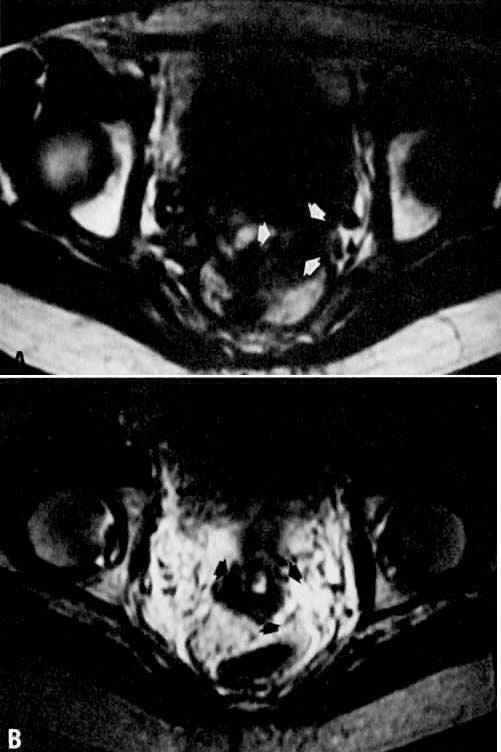

Fig. 9. A. Recurrent cervical carcinoma. Transverse T1-weighted image through the pelvis showing a large left pelvic soft-tissue mass ( arrows ). B. With T2 weighting, the mass in A now shows increased signal intensity consistent with recurrent carcinoma.